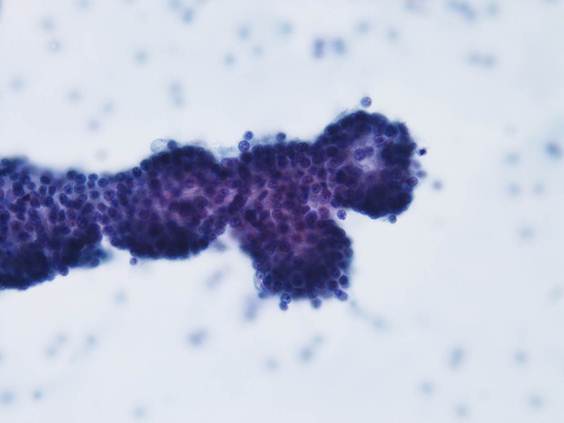

背景に組織球やライトグリーンに染まる顆粒が認められ、腺房を形成するような形態の細胞集塊が多数出現していた。

細胞質は境界不明瞭で、ライトグリーンに淡染する顆粒が認められた。

核は一部裸核状になり、小型類円形を呈し、クロマチンは細顆粒状で増量していた。

核小体は1個で赤く軽度腫大していた。